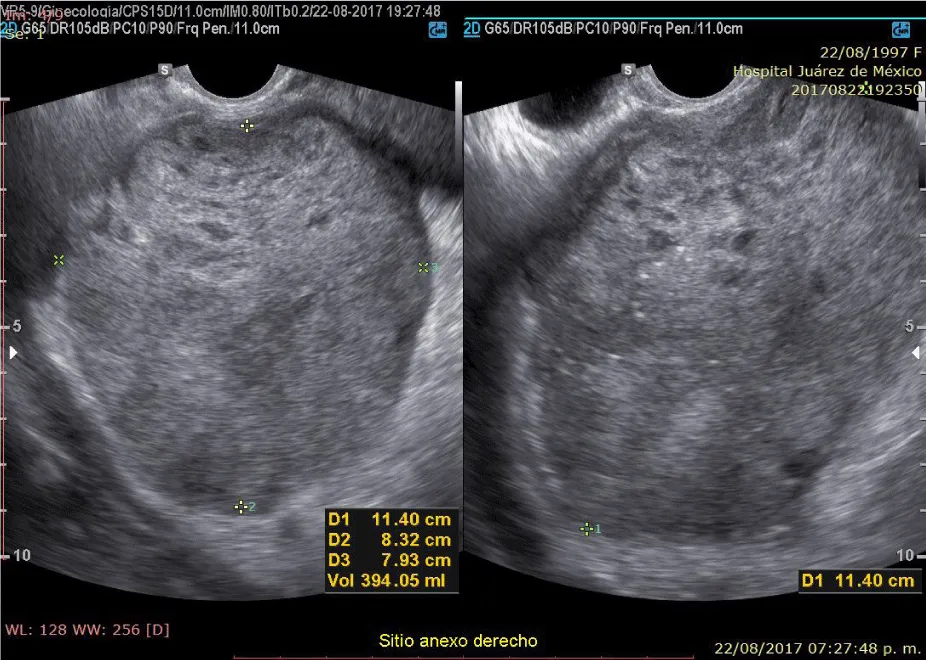

A 20-year-old married woman, with no history of pregnancy, who was admitted to the hospital for colicky abdominal pain in the right iliac fossa with radiation to the right iliac fossa from moderate to severe with Visual Analogue Scale with nausea and vomiting treated with analgesics presenting slight improvement; It is requested, quantification of the beta fraction of gonadotropin with figures of 112,337 mIU/mL and pelvic ultrasound with a report of a complex cyst of the right ovary without evidence of free fluid in the cul-de-sac; in relation to probable dysgerminoma or tumor of etiology to be determined; the hematic biometry with hemoglobin of 15.8 and hematocrit of 45, platelets of 313,000, leukocytes of 11,300 and 2 bands; reason for which she is referred to Hospital Juárez de México and once hospitalized; on August 18, 2017; she presents low-cost symptoms; and the studies are repeated quantification of beta fraction of Human Chorionic Gonadotropin (hGC) greater than 5,000, hemoglobin of 18 grams, hematocrit of 47%, leukocytes of 12,000, platelets of 367,000, lactic dehydrogenase of 473, direct bilirubin of 0.8 and the 2.3 total; normal liver transaminases; Ultrasound reports uterus in anteversion of 79x26x31mm, homogeneous myometrium, endometrial thickness of 7.9mm and right annex with lesion of 114 x83x79mm and total volume of 394cc, heterogeneous with linear images in its interior punctiform, the ultrasound diagnosis was, probable right annex teratoma tumor cystic.

On physical examination, the patient with generalized pallor of the skin and integuments, hypotensive, tachycardic, diaphoretic, without cardiorespiratory compromise, globose abdomen due to abundant adipose panniculus, perstalsis present, pain on palpation in the right iliac fossa on bimanual touch, the uterus is delimited 8x5 cm, right annex, 12x9 cm adnexal tumor, irregular, firm, pain on cervical mobilization, with spotting-shaped transvaginal hemorrhage, extremities without edema, normal tendon reflexes. According to the clinical presentation, imaging studies, on suspicion of ruling out ectopic pregnancy, an exploratory laparotomy was performed, with findings of the right annex of 20x15 cm adhered to the uterus and sigmoid rectum without evidence of hemoperitoneum and a right salpingo-oophorectomy was performed for probable right ectopic pregnancy with hematic loss due to the surgical procedure of 40cc and sent to pathology for definitive histopathological study, during follow-up a control gonadotropin quantification was requested with the last report of 1 103 918.7 mUI/mL. The histopathological results of the macroscopic surgical specimen were right salpingo-oophorectomy, with choriocarcinoma with extensive necrosis, 1 cm tumor extension to the ovarian surface not identified, lymphovascular invasion present and free surgical margins of the residual ovarian tumor with cystic follicles, Figure 1 and the report microscopic, Figures 2-4. A new hCG quantification is performed, negative head tomography and chest tomography with probable metastasis due to pulmonary nodule, in abdomen and pelvis, presence of peritoneal carcinomatosis, with free fluid and lumbar puncture reports negative for malignant cells and chemotherapy based on cisplatin and etoposide 5 sessions and the patient is disease-free after two years of follow-up.